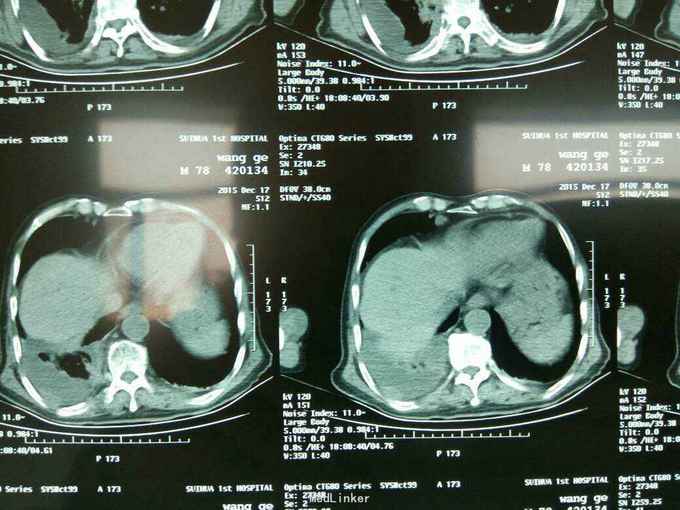

根据病史查体诊断:腰间盘突出症待确诊。应用消肿营养神经镇痛治疗。一天。查核磁共振示:腰椎多节段间盘突出伴椎管狭窄。第二腰椎骨破坏侵及椎板。部分突入椎管,脊髓受压。诊断:腰间盘突出伴椎管狭窄。第二腰椎转移癌,脊髓受压。经与家属沟通,查双肺CT:双肺下叶炎症。肺部纤维化。可见肿瘤阴影。肋骨及胸膜受累。胸椎部分骨破坏。最终诊断:双肺癌,胸椎,腰椎骨转移,脊髓受压。多节段腰椎间盘突出。病人至肿瘤科治疗。